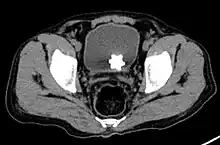

The diagnosis of bladder stone includes urinalysis, ultrasonography, x rays or cystoscopy (inserting a small thin camera into the urethra and viewing the bladder). The intravenous pyelogram can also be used to assess the presence of kidney stones. This test involves injecting a radiocontrast agent which is passed into the urinary system. X-ray images are then obtained every few minutes to determine if there is any obstruction to the contrast as it is excreted into the bladder. Today, intravenous pyelogram has been replaced at many health centers by CT scans. CT scans are more sensitive and can identify very small stones not seen by other tests.[8]